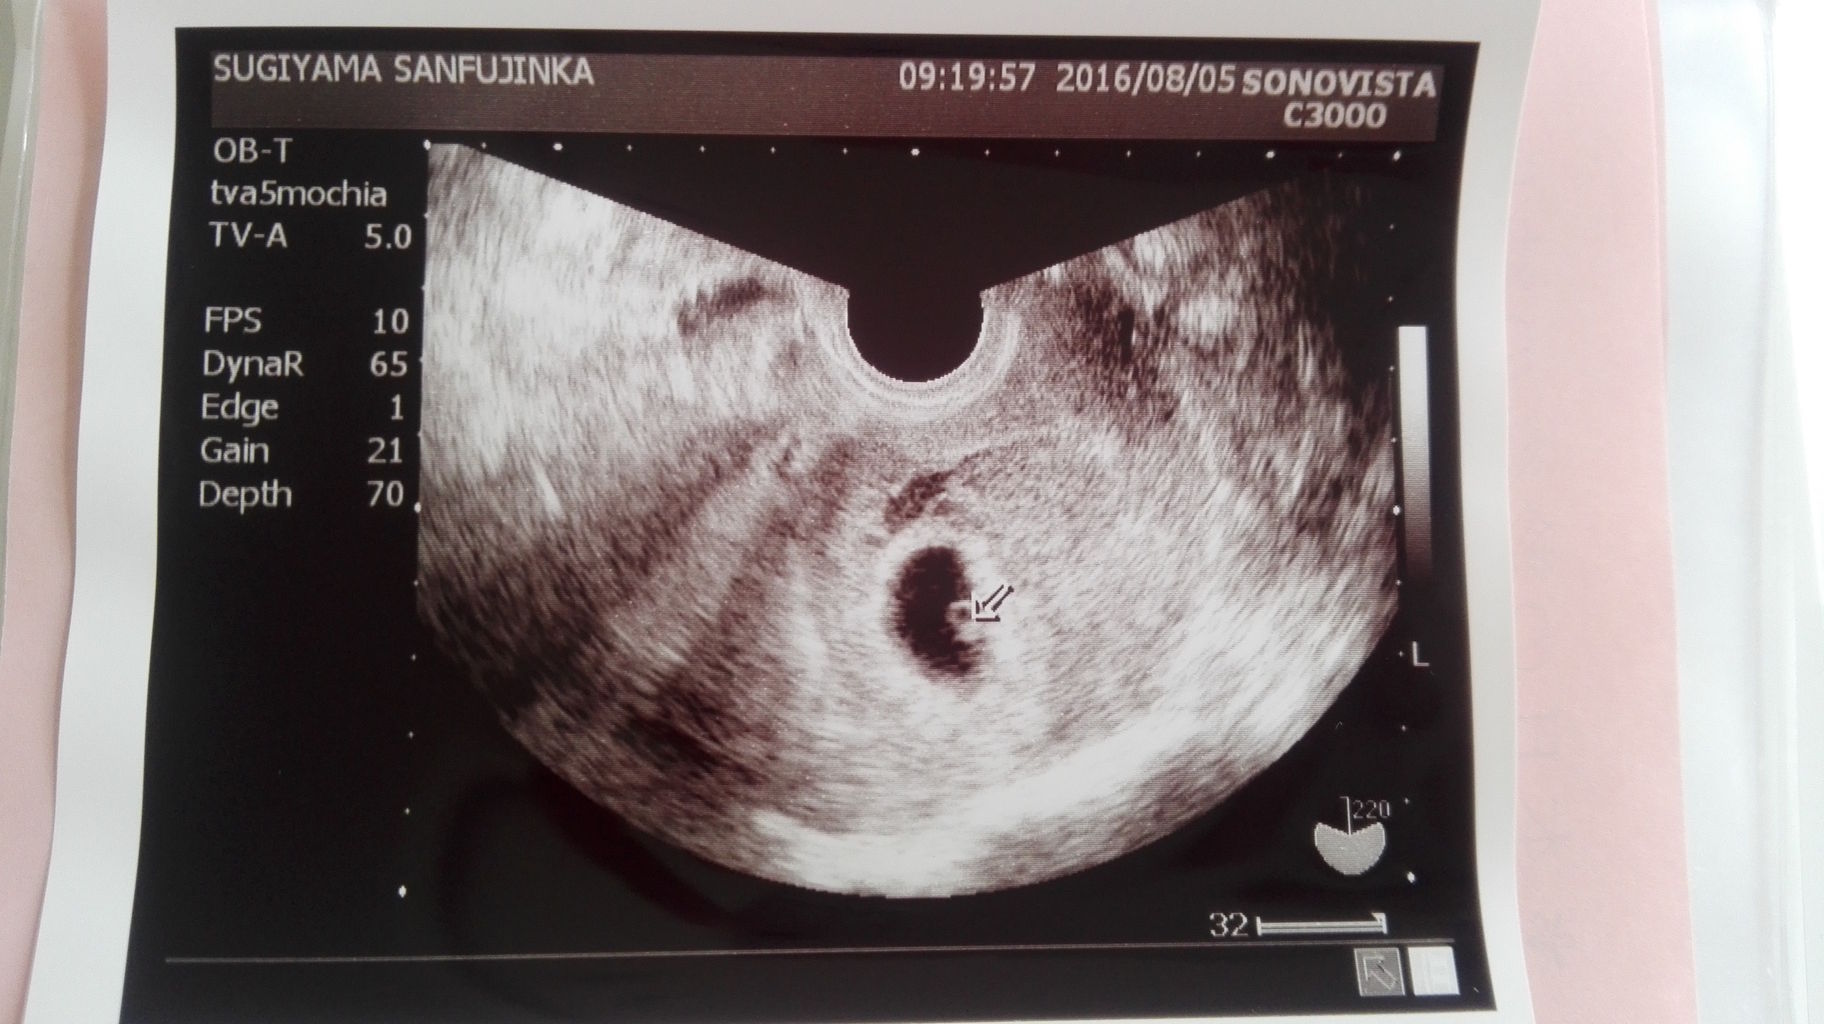

現在7週4日の妊婦です。 体外受精による妊娠なので、週数にズレはないと思います。 以下が、今までの経過です。 3/23 凍結胚盤胞移植 4/4 判定日 血中hcg460くらい 4/11 5週3日 胎嚢のみ 115mm 確認 4/18 6週3日 胎嚢211mm、卵黄嚢、胎芽 (小さすぎて計測はじめまして。 たぶん今6週目の新米妊婦です。 きのう2回目の検診で胎嚢がmmなのを 確認できたのですが、胎芽らしきものがまだ見えませんでした。 先週の胎嚢は7mmだったので、 1週間で13mm大きくなったのですが このまま見えずに流産してしまうのではと不安です。妊娠 不妊治療で体外受精で妊娠することができました。 5週1日で胎嚢の大きさが66ミリしかなく少し 小さめだな・・・と少し心配でした。6週3日で今日 診察に行き胎芽が見えるかな・・・と思っていた

4週6日目胎のう見えず 5週6日目胎のう103ミリ 6週6日目胎のう21ミリ 胎芽・卵黄脳見えず という経過です。 先生には、「排卵のズレがない場合、 6週6日目にはほとんどの人が心拍確認できるので、 ちょっと心配だね。6週5日です! 体外受精2回目での妊娠 6週一日で胎嚢9mm卵黄囊のみ確認 厳しいとの先生のお言葉で、 本日6週5日目で診察 胎嚢105mm胎芽らしいきものだけで、 心拍確認できず。 稽留流産の可能性が高いとの事 先生にはど体外受精にて着床しました。 (胚盤胞移植日年4月28日) その後無事胎嚢も確認でき、先日6週2日の検診に行ったところ、胎嚢の中は空っぽでまだ胎芽が見られないと言われました。 来週また様子を見ましょう、と言われ、最後に撮った超音波の写真をいただいたのですが、家に帰って冷静に

妊娠6週0日で胎芽、卵黄嚢、心拍が確認出来ませんでした。 体外受精をしましたので、週数に間違いはありません。 また、6週0日で胎嚢が14,6ミリしかありませんでした。 5週1日で4ミ リでしたので、成長はしているようです。40歳の体外受精から出産記録 40歳で体外受精に挑戦し、やっと妊娠継続。毎日検索毎日落ち込み毎日夢見ていた、妊娠前からポッコリお腹のおばさんです。 1年かかって不妊治療クリニックを卒業出来ました。 不妊治療から妊娠、出産(子育て)の記録です。妊娠6週目で胎芽が見えないことについて お世話になります。 現在妊娠6週1日で、まだ胎芽、心拍が確認されませんでした。 胎嚢は25ミリ。 体外受精でしたので、週の数え方に間違いはありません。 先生曰く、エコーから遠いとこらにあるんだよね

妊娠4週になると見えてくる、「胎嚢」「卵黄嚢」って何? 妊娠5週になると脳や神経、心臓など臓器、それに手足や目、耳の原型もできるってホント? 妊娠6~7週で、心臓の動き出す!? まだ「胎児」と呼んでもらえない妊娠2ヶ月の「胎芽」時代の赤ちゃんのこと、母体のこと。6週3日ですが、胎嚢は17mm,胎芽は44mmでした。 心臓らしきものが動いていました。 先々週は全く胎嚢も見えず、不安な1週間でしたが、まずは子宮外妊娠ではなかったとホッとしています。 来週また検診で、母子手帳かなぁーっと先生からの一言でした。 おなまえ 愛実 ねんれい 28 妊娠週 6w3d 3日前見えなかった胎芽と心拍が確認できました。 胎嚢263mm、胎芽38mm加藤レディスクリニック(KLC) みお KLC体外受精スケジュール! 妊娠5週目~7週目心拍確認~9週目卒業まで 加藤レディスクリニック(KLC)にて自分で最後と決めた通算9回目の採卵、7回目の移植で初めての陽性反応が出て、D35(妊娠4週